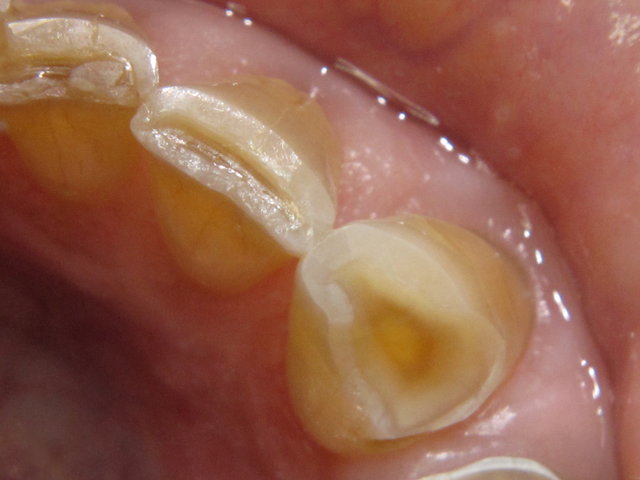

Säuregeschädigte Zähne ...

Vollkeramik-Kronen by CLINICDENT ✓

Zitronensaft ist sauer und schadet den Zähnen ...

Durchschimmernder Zahnnerv ...